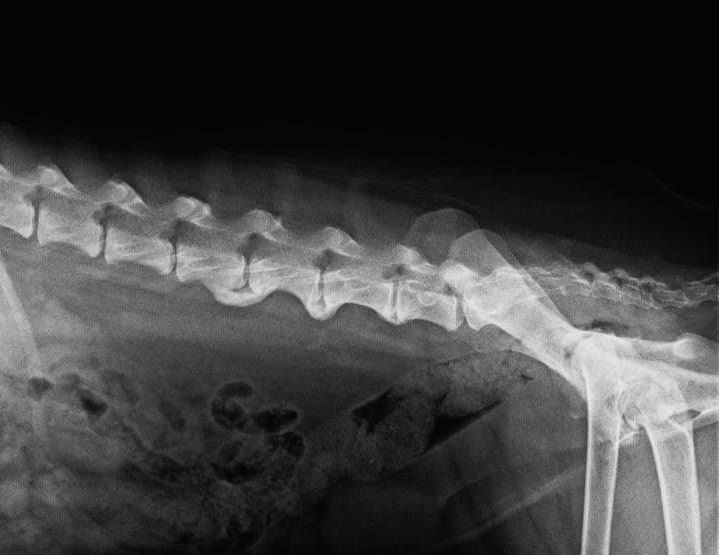

2. Spondylose:

Spondylose bezeichnet die Bildung von Knochenbrücken zwischen den Wirbelkörpern, die zu Schmerzen und Steifheit im Rückenbereich führen und auch die Spinalnerven beeinträchtigen können (Hund knickt hinten weg, schleift mit den Pfoten). Diese Erkrankung tritt in Schüben auf und ist für den Hund sehr schmerzhaft.